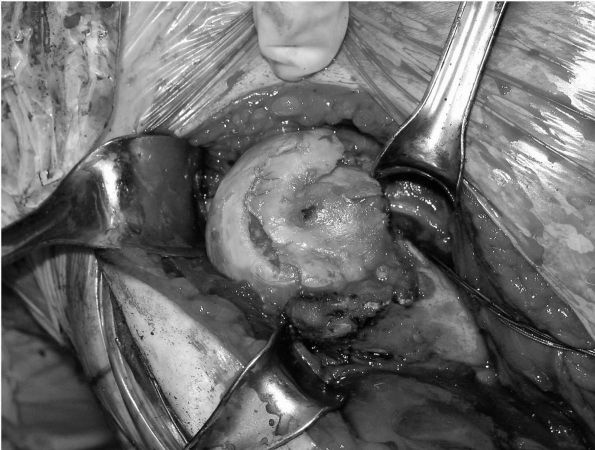

FIGURE 12-6. (A) and (B)

Intraoperative photographs of glenohumeral arthritis with flattening of the head, loss of articular cartilage, eburnation of the subchondral bone, and large peripheral osteophytes. |